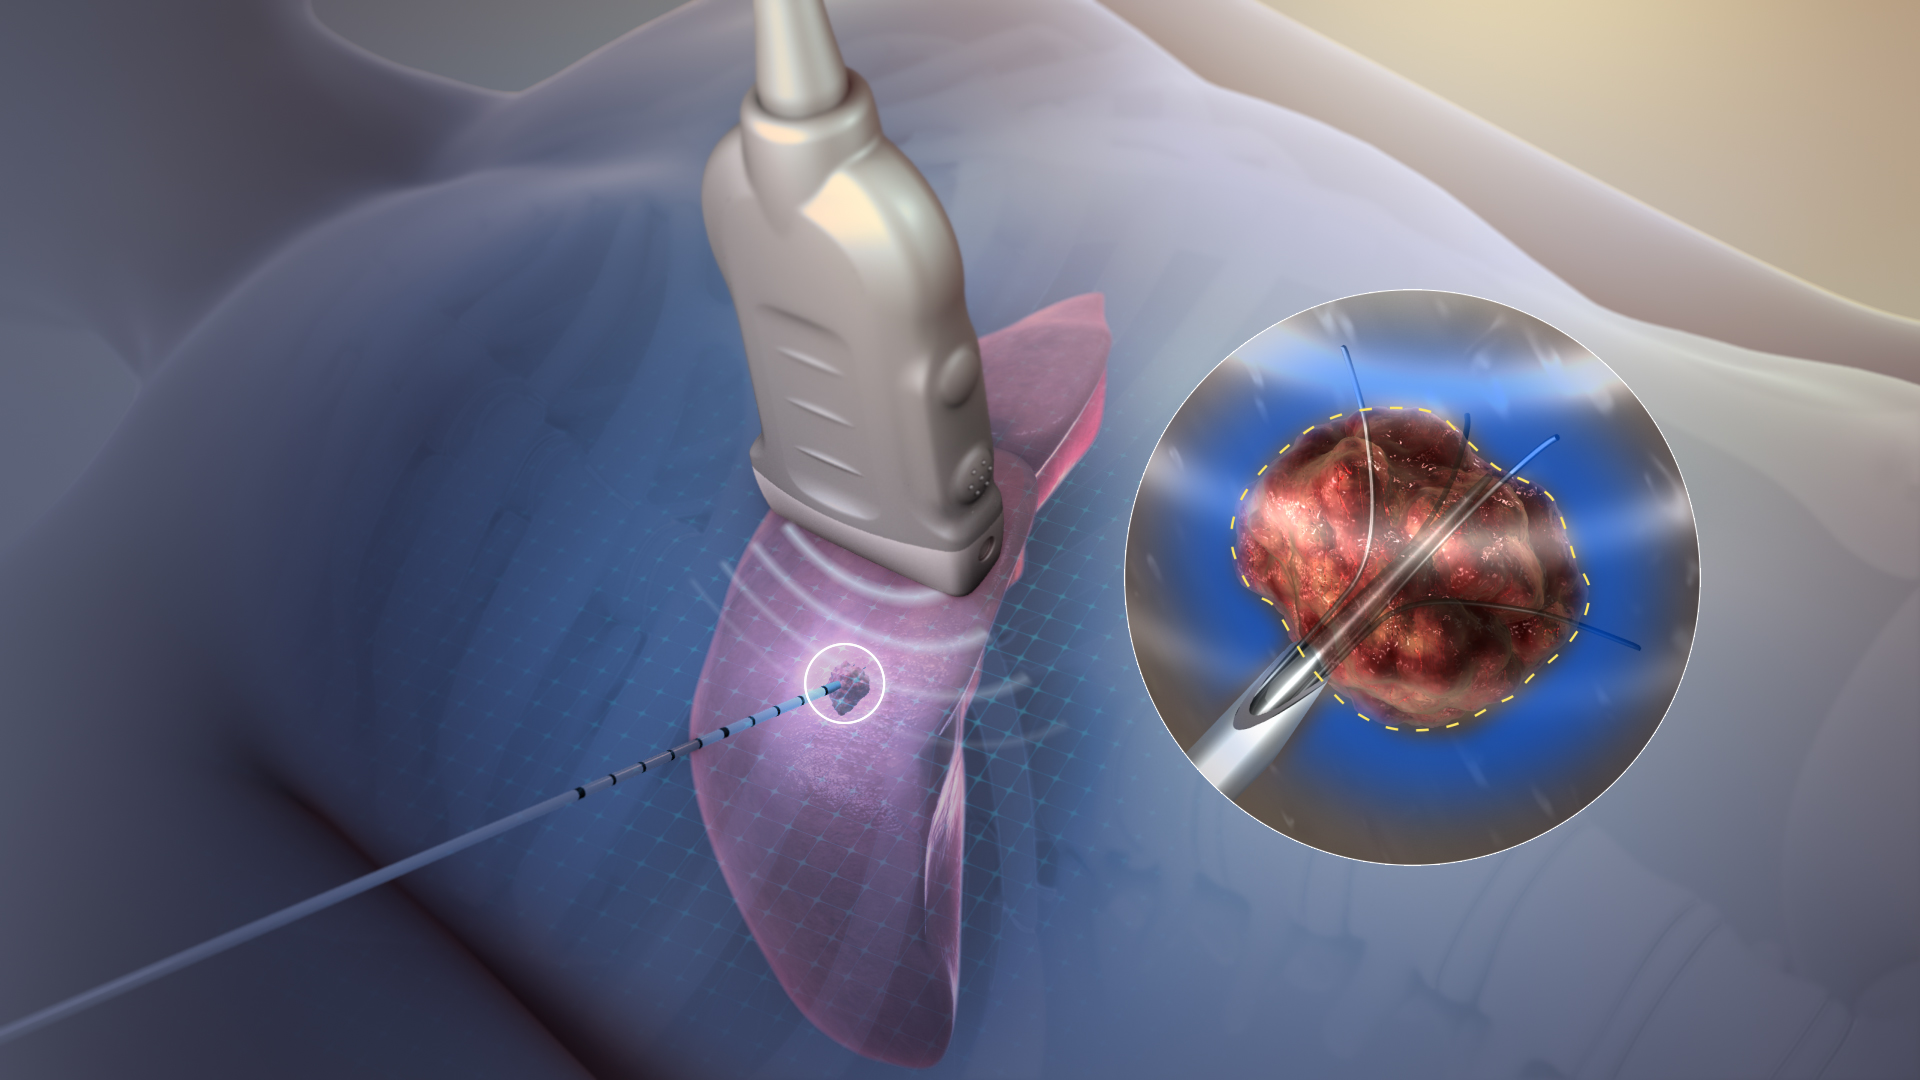

Endovenous Laser Treatment (EVLT)

A procedure that uses a laser to seal off damaged veins and treat varicose veins.

Radiofrequency Ablation (RFA)

A heat-based procedure for closing malfunctioning veins and improving circulation.